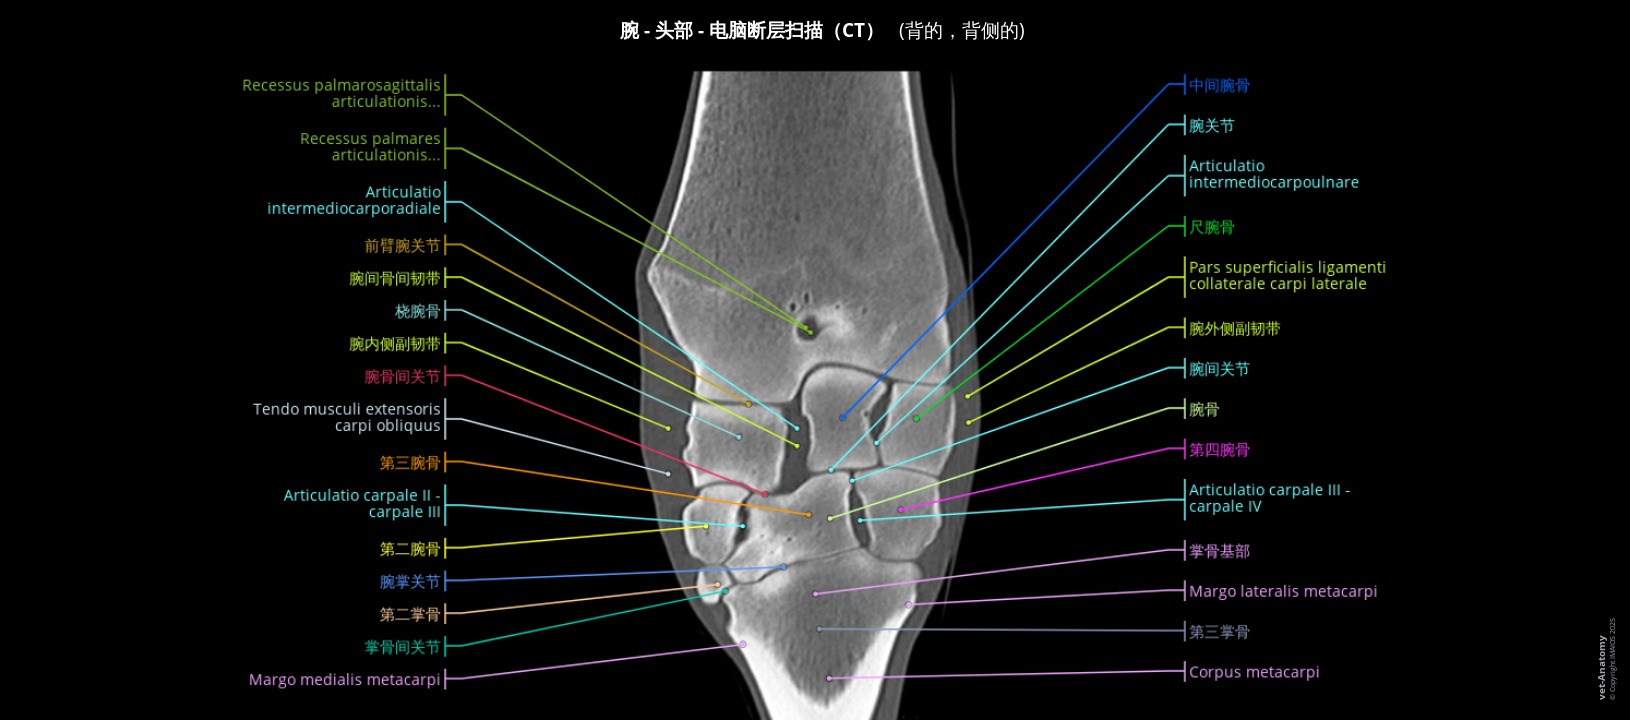

CT成像马腕骨的横截面解剖标记

- Antoine Micheau, MD , Denis HOA, MD , Susanne AEB Boroffka, PhD - dipl. ECVDI

- 发布日期: 2025年2月17日 | 最新更新 2025年3月18日

- https://doi.org/10.37019/vet-anatomy/a1a32a91-fcb1-4cda-8854-8b8f7106d3ca.zh ISSN 2534-5087

简介

腕关节病变是导致马跛行的常见原因。准确的诊断有助于早期预防和治疗病变,并限制疾病恶化的风险。

传统的放射线检查和超声波检查主要用来评估马的骨关节病变。然而,腕关节非常复杂:大量的骨性叠加可能会隐藏病理过程,可能会难以辨认深层韧带或肌腱结构。计算机断层扫描(CT)和CT关节造影术正逐渐成为完成这些骨关节评估的便捷技术,多平面重建可提供更准确的病变评估。在某些条件下可以在站立的马匹上进行这些检查,这也是支持这些检查的另一个理由。

在本单元中,我们将介绍马腕骨在三个主要平面上的正常CT解剖。

材料与方法

来自法国Livarot-Pays-d'Auge的Mickaël Robert博士(ECVS, CHVE de Livet)对一匹两岁大的法国特罗特马的胸腔肢体进行了CT扫描。

图像在三个主要平面(横切面、矢状面和背切面)上进行了重建,而且有腕骨的三维图像作为辅助。影像由IMAIOS的兽医解剖学家Stephan Mahler, DVM, MSc, PhD根据国际兽医解剖学名词(NAV)进行标注。

解剖结构被分为不同的主题:

- 身体部位

- 区

- 骨

- 关节

- 韧带

- 肌肉

- 肌腱

- 筋膜

- 腱鞘和滑囊

- 动脉

- 静脉

- 神经

结果与讨论

尺骨的近端部分在马身上清晰可见,但其远端部分已无法与桡骨区分开来。因此,兽医解剖学术语将两个茎突连接到桡骨上,并将其命名为内侧和外侧茎突。然而与其他物种一样,外侧的桡骨茎突是由尺骨发育而来的。因此也可以使用尺骨茎突这一术语,本单元中也同时使用了这两个术语。

食肉动物和马的副腕骨有两个关节面:

- 一个与尺桡骨的主要关节面

- 第二个关节面与尺骨茎突相连,尤其是在马身上。由于马的尺骨茎突通常与桡骨完全融合,因此一些作者认为马的副腕骨与桡骨相接。

我们认为这第二个关节属于腕前关节,附属腕骨的关节仅限于副腕骨和尺侧腕骨之间的关节,因此它相当于人类的豌豆骨关节(豆三角关节)。

在本单元中可以看到这次检查的马匹的对侧胸肢跛行。然而在明显健康的肢体上也发现了偶发病变:桡骨和第三腕骨的背侧边缘中度硬化,有小面积溶解,没有明显的碎裂。

腕骨外侧表面邻近桡骨的远端处可见一些线状伪影,这可能会干扰判断,尤其是在识别腕外侧副韧带时。